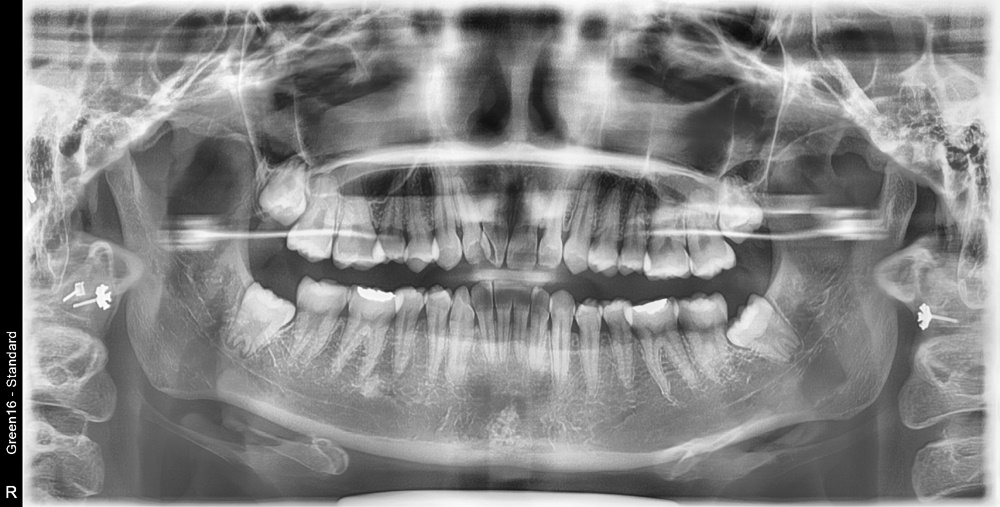

치료 전 사진입니다.